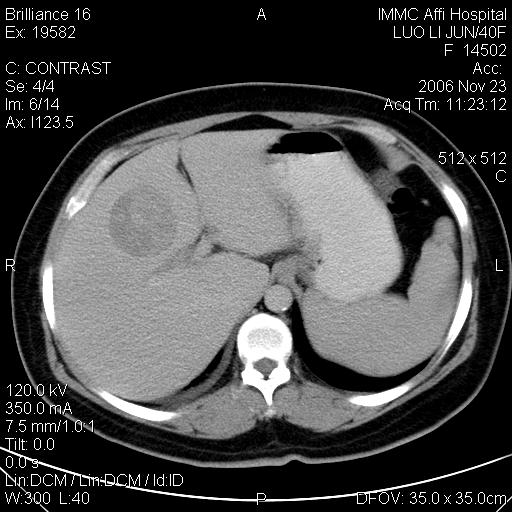

标题: CT5664:我也发一个肝脏的片子大家看看

很典型的肝癌。

速升速降,典型肝癌.

是啊,典型的早出早归!

快进快出典型肝癌.

符合肝癌的增强特征。支持肝癌!

病灶好圆!可能恶性度不高。

不能除外肝细胞腺瘤吧,还是得结合病史。

很好的片子,可惜增强做的比较失败,a期时间没有把我好,实际到了静脉早期了,否则会更典型。

最终考虑是肝腺瘤